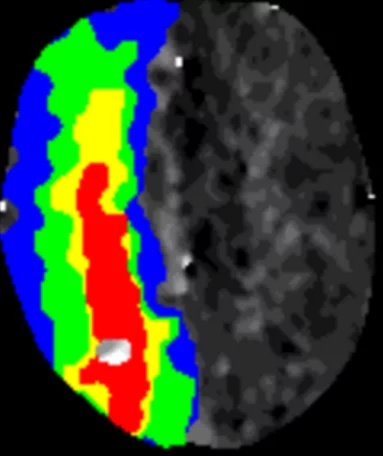

- Angiographie (Darstellung der Gefässe mit Kontrastmittel)

- Abklärung und Beratung bei Gefässfehlbildungen (Aneurysma, arteriovenöse Malformation, arteriovenöse Fistel)